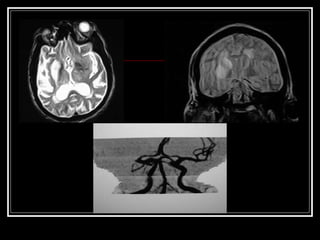

Exames de Imagem Qual a primeira escolha na emergência? Por quê? Qual o método mais sensível?

Exames de ImagemQual a primeira escolha na emergência? Por quê? Qual o método mais sensível?